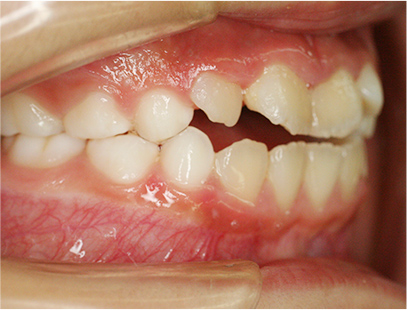

前歯部の開咬とデコボコ

前歯部が咬んでいないことを主訴として来院されました。精査、診断の結果「前歯部にデコボコを伴う開咬」と診断されました。

• 右側